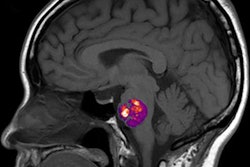

Trained using 414 patients clinically diagnosed with Alzheimer's disease and normal controls in the ADNI, the researchers' fully convolutional neural network (CNN) generates color-coded disease probability maps after analyzing T1-weighted brain MR images. Next, a multilayer perceptron analyzes these disease probability maps to produce a binary classification of Alzheimer's disease status.

In other results, the model's identification of high-risk cerebral regions closely tracked postmortem histopathological findings, according to the researchers.

"Not only can we accurately predict the risk of Alzheimer's disease but this algorithm can generate interpretable and intuitive visualizations of individual Alzheimer's disease risk en route to accurate diagnosis," Kolachalama said in a statement.